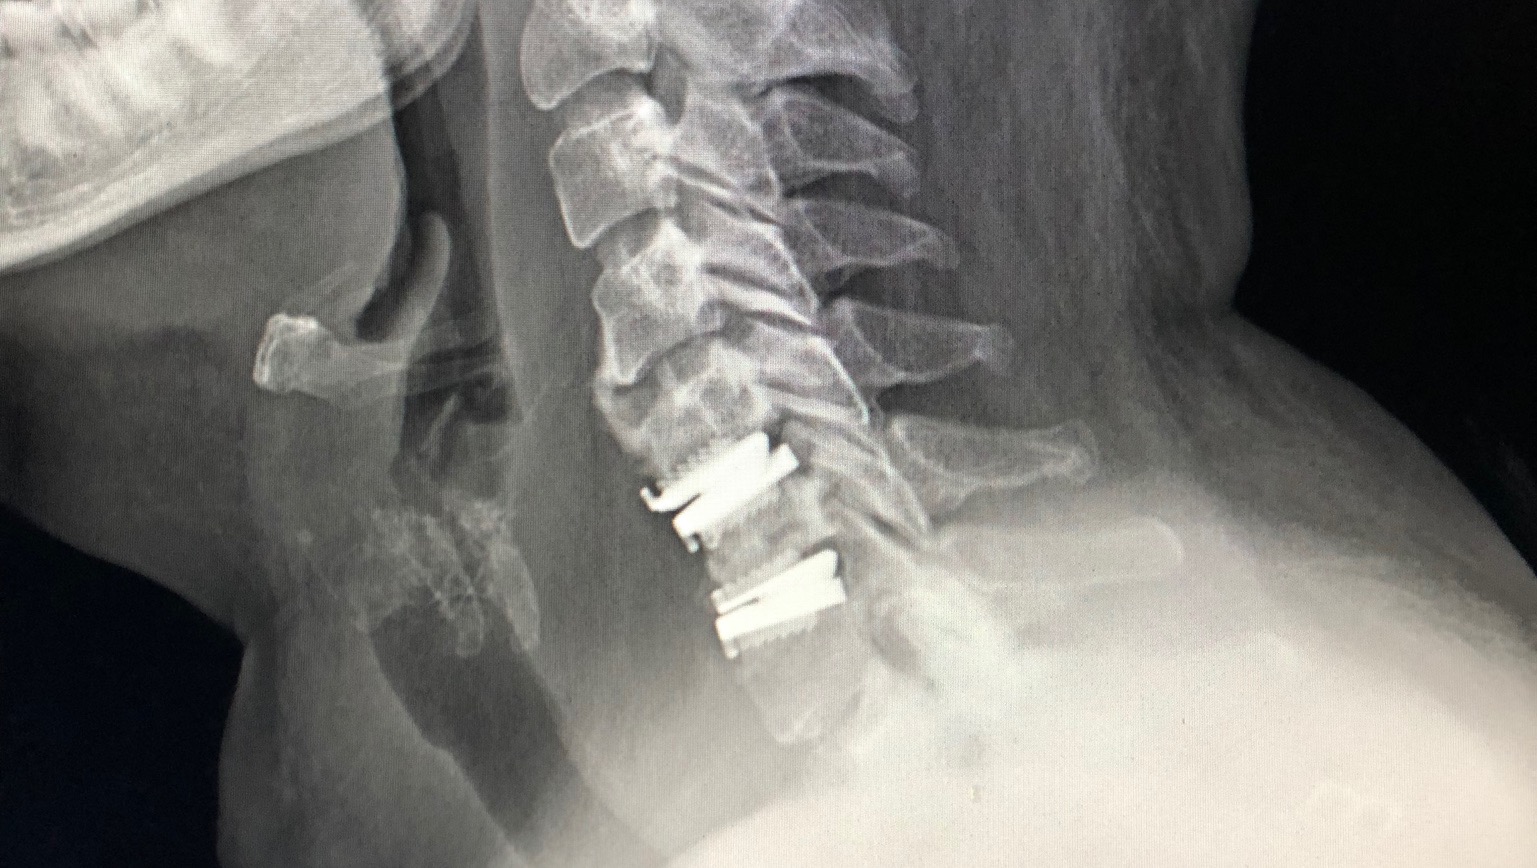

- She fell 8 yrs ago and seriously damaged her neck and lumbar spine. She has had 2 spine surgeries across 4 vertebrae as a result. Cervical disk replacements and lumbar fusion. The degenerative condition associated with that has progressed gradually but more so the last couple years and she is now approaching paralysis if she don’t get the right treatments. She suffers from muscle atrophy, weakness, pain and tremors. She is no longer independent and needs help doing almost everything and cannot walk on her own. She is one tough lady.